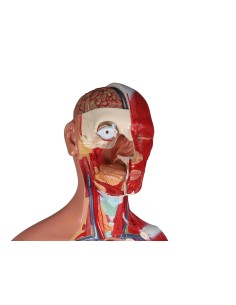

3B Scientific, Torse bisexuel, modèle de luxe, séparable en 20 parties B32

3B Scientific, Torse bisexuel, modèle de luxe, séparable en 20 parties B32

3B Scientifique, torse bisexuel japonais, décomposable en 18 parties B32/4

3B Torse scientifique, africain bisexuel, décomposable en 24 parties B37